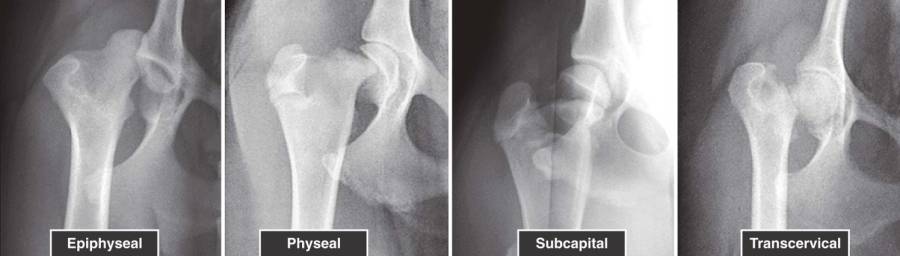

- Frakturarten